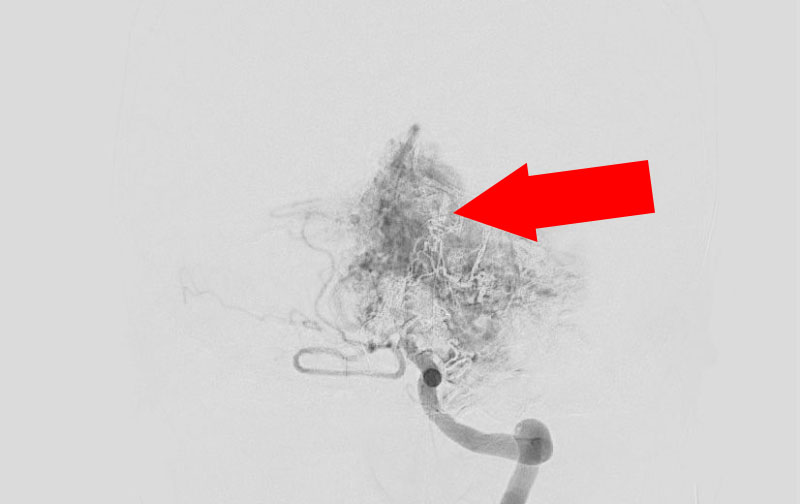

No.1576 手術前

No.1576 手術中

No.1576 手術後